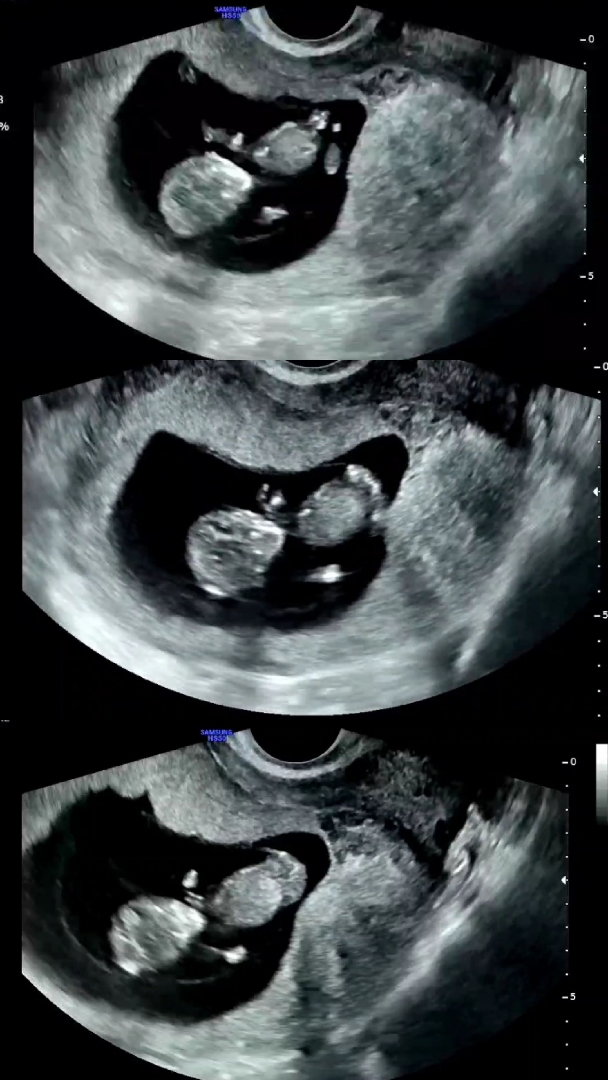

예전에 7주차에 염색체이상으로 유산을했던 경험이 있어용 형태도 찌그러져있고 해서 정상적인 아가에게 생긴 사고는 아니였어서 잘 이겨냈었어용 8주차때 원장님께서 지금 아가는 다행히 동글동글 예쁘고 최근 본 그 어떤 태아보다 너무 건강하지만 입체초음파 보기전에 한번 더 보자고 신경써주셔서 10주차 말-11주초에 보자고 하셨는데 애기가 머리부터 꼬리뼈까지 4.3센치나 되서 쑥쑥 커있더라구요 심장소리도 170-173으로 우렁차고 초코우유 안먹어서 얌전하긴 했지만 이쯤 되니까 벌써 신랑 닮은거 같고 너무 예쁜거있죠ㅎㅎ 입덧 체덧은 거의 사라지고 가슴통증도 조금 더 잔잔해져서 컨디션 안정되고 복통도 크게 있진 않아요. 두통도 드디어 벗어나고 있답니다. 가끔 좌골 인대가 땡기는 느낌? 신랑이 골반 만져주면 굉장히 시원하게 느껴질 정도로 나도 모르는 사이 텐견이 있는정도? 한번씩 자기전에 회음부나 골반안쪽에 쥐나듯 콱 쥐어짜는거 잠깐씩 빼고는 진짜 초반보다 너무편해요 배탈도 다 없어졌고 12주가 왜 안정의 시작인지 알겠어요 4주부터 11주까지 차근차근 증상이 완화되지만 태반 형성 다음주부터 뱃속에 묵직한 뭔가가 차지한 느낌이 있어서 아이가 잘 있는게 본능적으로 엄청 확실해요ㅎ 아! 근데 잠이 사라지기 시작해서 밤에도 낮에도 잠이 안오는 변화에 진입했습니다ㅎㅎ 여전히 피망,고추같은 향은 역하지만 고기도 밥도 먹을수 있고 전체적으로 완화됐어요ㅎ 철분제로는 철분부족이 일어난다고 꼭 소고기를 먹으라고 해서 미역국에 소고기를 넣어 오래 끓여 냄새없는 소고기를 먹고있어용 비타민D도 영양제로는 흡수가 더뎌서 햇빛을 꼭 30분씩 보라고 합니다! 다들 걱정이 엄청엄청 많으신데 절대적 증상도 없고 완화는 좋은증상이에요 아 근데 유산때 경험으로 배가 쥐어짜듯 아프다가 30분 후 피비침 전혀없이 괜찮아지더니 반나절안에 모든 증상 싹 사라지면서 무슨 마사지 받고 나온듯 개운하고 컨디션이 완전 뛰어다닐거같이 가벼워지고 나더니만 아기가 사라졌었어요 마치 감기가 낫듯! (모체는 태아를 초반에 바이러스 침입으로 인식하니까요!) 그니까 몸은 피곤하고 무겁고 기분도 썩 별로고 컨디션도 꽝인데 입덧이나 가슴통증 쬐금 사라지고 그런걸로 불안할 필요가 없습니다ㅎㅎ 제 경험상 진짜 큰 태아의 태반박리같은 엄청 위험한 상황이 아니고는 초반에 유산된다면 갑자기 감기낫듯 개운하고 펄펄 뛰어다닐수 있어요 남편마져도 제 움직임의 가벼움을 느껴서 이상하다고 했었어용 (반대로 응급상황으로 고통스럽거나, 줄줄 쏟아지는 출혈이 있거나 하신 지인분도 계셨어요!) 그런거 아닌이상 작은 증상 변화는 걱정 마시고! 건강하게 이쁘게 키워봅시담! 다들 11주12주 아가 공유 많이 해주세요!! 아기가 커갈수록 공유가 없더라구요ㅎㅎ